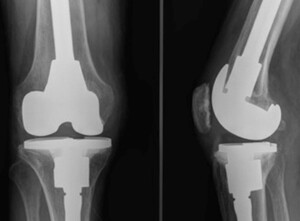

After establishing the reason for failure, a further critical step in pre-operative planning is assessment of bone stock and bone loss. This can initially be done on pre-operative radiographs, however final intra-operative assessment may reveal more substantial loss.28 Engh et al described the Anderson Orthopaedic Research Institute (AORI) classification which has now become the most broadly adopted classification system globally. This defines the bone loss as tibia (T) or femur (F) independently, and the severity is graded 1 to 3. 1 is a minor defect at the level of the bone-implant surface, with no significant defect extending into the metaphysis, implant stability is not compromised. Type 2 has metaphyseal damage which required adjunct for stability, this can be further split into 2A – when one femoral condyle or one side of the tibial plateau is affected, or type 2B – both condyles or both sides of the plateau.38 Type 3 is deficient metaphysis, with major loss of plateau or condyle, often with ligamentous detachment39 (figure 1) (table 1). The term contained describes a central bone loss with intact peripheral cortical rim surrounding it, uncontained describes a defect in the cortical rim.40